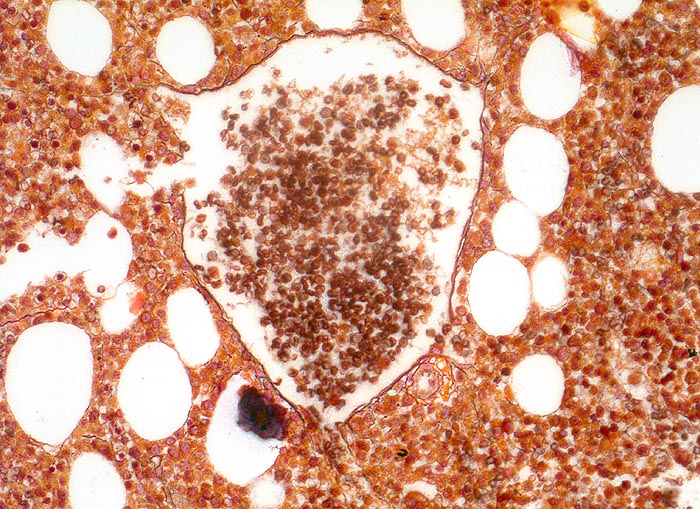

• Osteosklerose: verplumpte und breite Knochenbälkchen.

• Dilatierte Sinusoide mit intrasinusoidaler Blutbildung.

• Vermehrung von atypischen, in Gruppen liegenden Megakaryozyten mit abnorm lobulierten Kernen.

• Nacktkernige (zytoplasmaarme) und vergrösserte Megakaryozyten.

• Hyperplastische ausreifende Myelopoese.

• Hypoplastische Erythropoese.